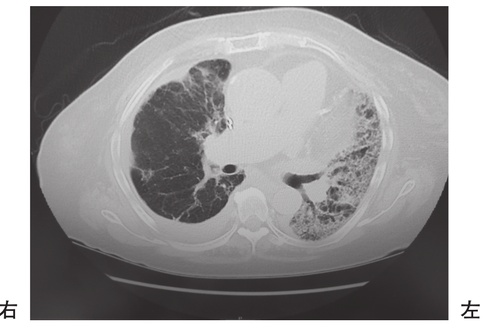

第59回 午後 理学療法士実地問題

重要

72歳の男性。在宅酸素療法中。呼吸困難が増悪したため入院し、作業療法が開始された。開始時の胸部CT を別に示す。mMRCはGrade 4であり、酸素流量は安静時3L/分、労作時5L/分であった。この患者の日常生活指導で最も優先されるのはどれか。

e6p4xvXGI1

1

口すぼめ呼吸を指導する。

2

更衣動作は素早く行わせる。

3

呼吸困難時には深呼吸を促す。

4

立ち上がってすぐに移動する。

5

短時間で動作を区切って休憩する。